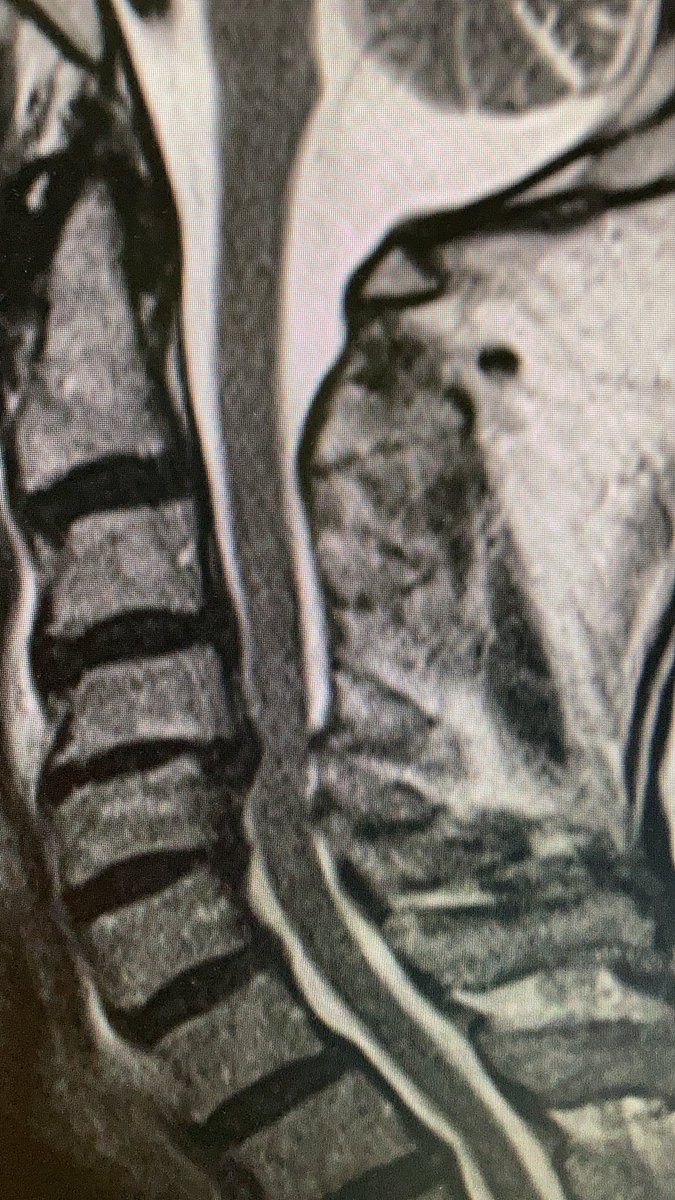

this is a #odontoid process/dens axis in a patient with radiculomyelopathy.

osteoarthritis of the atlantodental joint is present, too